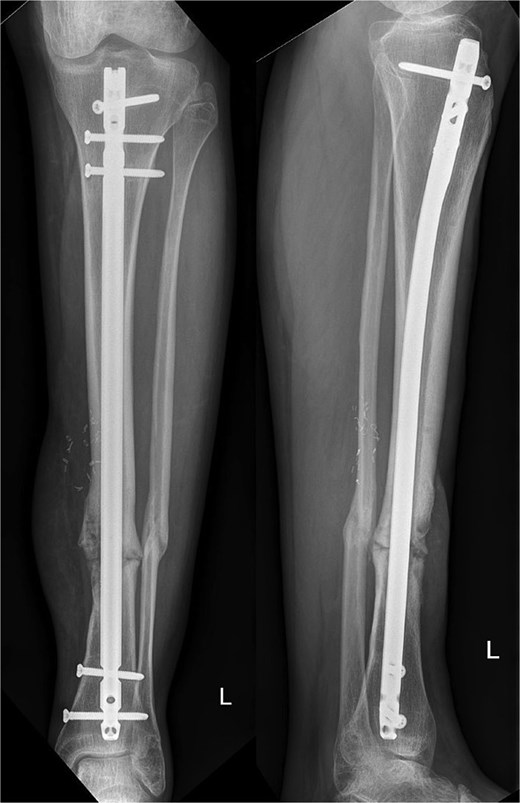

Autologous bone from the ipsilateral femur was harvested using the RIA II-system (11 mm and 12.5 mm reamer head) (Fig. 2a). The predesigned graft cage (TRUMATCH™ Graft Cage – Long Bone, DePuy Synthes, Zuchwil, Switzerland), was inserted and filled with autologous bone (Fig. 2b and c). Postoperatively, the patient was allowed touch down partial weight bearing.

(a) RIA-harvested bone graft; (b) graft cage; (c) operation site with graft cage; (d) postoperative X-ray after graft cage implantation.

Ten months postoperatively, the patient was pain-free and demonstrated a normal gait pattern, associated with radiological signs of osseous consolidation (Fig. 3).

Our patient presented with an excellent result after 10 months without any restrictions and was completely pain-free. Our radiographic analysis demonstrated that no resorption occurred and no secondary movement of the graft (Fig. 3). Moreover, the even distribution of the graft was associated with no heterotopic bone formation or issues that would be related to donor site pathologies in distraction osteogenesis.